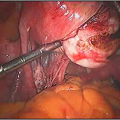

How are Hysteroscopic operations performed ?

The hysteroscope allows good vision inside the uterus .The uterus is kept distended by a continuous flow of a liquid by� specialised pressure-controllong device. Specialised fine electrosurgical tools are passed into the cavity under vision and the pathology is tackled. The patient goes home the same day.

- Asherman’s syndrome�(i.e. intrauterine adhesions). Hysteroscopic adhesiolysis is the technique of lysing adhesions in the uterus using either microscissors (recommended) or thermal energy modalities. Hysteroscopy can be used in conjunction with laparascopy or other methods to reduce the risk of perforation during the procedure.